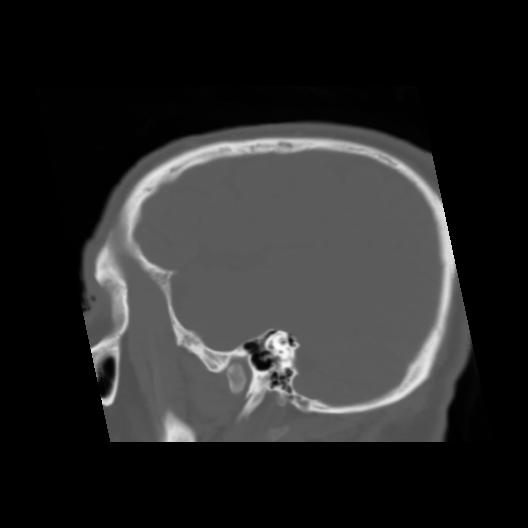

6 CEREBRO,,Sagittal,3.000,CEREBRO,Sagittal,